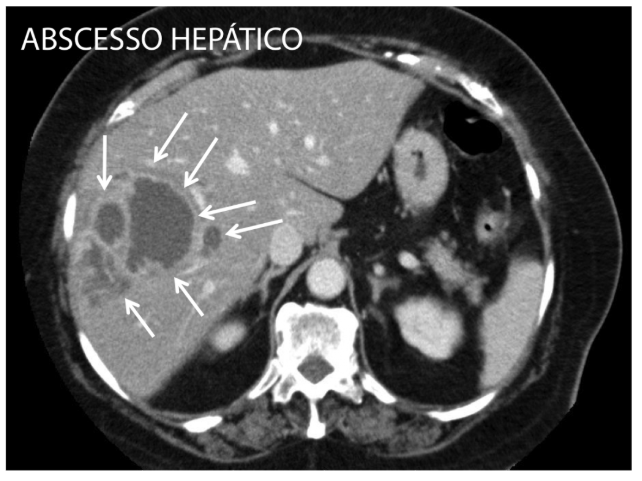

Exames de Imagem

- Ultrassom (USG): Bom exame inicial, útil para diferenciar de cistos simples e tumores sólidos.

- Tomografia (TC) de Abdome: É o melhor exame para definição.

- Achados: Coleção encapsulada, conteúdo heterogêneo e presença de edema perilesional característico.